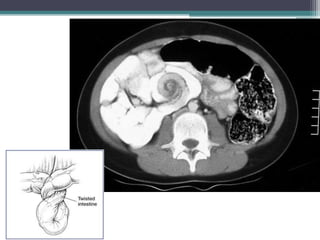

Tài liệu bàn về tắc ruột, bao gồm định nghĩa, phân loại và nguyên nhân của tình trạng này, với sự phân biệt giữa tắc cơ học và cơ năng. Các triệu chứng và chẩn đoán lâm sàng được trình bày, kèm theo phương pháp chẩn đoán cận lâm sàng như x-quang và siêu âm. Ngoài ra, tài liệu cũng đề cập đến các biến chứng và hậu quả của tắc ruột.